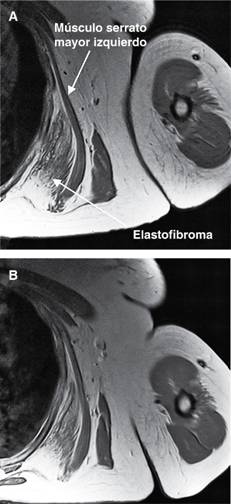

Paciente femenino de 58 años, empleada de negocio de telas desde hace 20 años; acude por presentar abultamiento de cinco años de evolución en región escapular izquierda, que le ocasiona discreta molestia al efectuar carga de rollos de tela en su trabajo. A la exploración se nota escápula izquierda prominente, no dolorosa al movimiento, con sensación de frote a los desplazamientos escapulares, con arcos de movilidad de hombros completos y sensibilidad normal; el resto de la exploración es normal. Se solicita resonancia magnética (Figuras 1 y 2) que permite diagnóstico de probable elastofibroma dorsi (ED); se propone cirugía, la cual rechaza. El ED es un tumor infrecuente de los tejidos blandos de la pared torácica, descrito inicialmente por Jarvi y Saxen1 en 1961; su localización más frecuente es periescapular en 99% de los casos y anterior a la escápula sobre el plano costal, entre la sexta y la octava costilla, profundo respecto a los músculos serrato anterior, romboides y dorsal ancho. Se observa entre la cuarta y sexta décadas de la vida, con prevalencia estimada de 2%, predominante en mujeres con relación 2:1, y predominio en hemitórax derecho; es bilateral en 10 a 60% de los casos; habitualmente asintomático; si existen síntomas se presenta dolor y frote con los movimientos escapulares. De etiopatogenia desconocida, se ha sugerido que la degeneración de las fibras de colágena es resultado de microtraumatismos repetitivos sobre la articulación escapulotorácica, induciendo proliferación excesiva de las fibras elásticas, por lo que se considera como un proceso reactivo, más que como una verdadera neoplasia.2 Histológicamente es una lesión benigna, no encapsulada, hipocelular y de contenido variable de colágeno, grasa y fibras elásticas. El diagnóstico diferencial3 debe realizarse con lesiones o tumores subcutáneos, como lipomas, fibrolipomas y neoplasias mesenquimales tipo liposarcomas, fibrosarcomas, histiocitoma fibroso, neurofibroma o metástasis. La ecografía, la tomografía computarizada y la resonancia magnética nuclear son las exploraciones complementarias más utilizadas para confirmar el diagnóstico. En la ecografía se observa un patrón alternante, de tipo fasciculado o laminar, de líneas hipo e hiperecogénicas paralelas a la pared torácica; la señal Doppler suele ser negativa, por ausencia de vascularización. La TC muestra alternancia de tejido adiposo con densidad grasa y de tejido fibroso con densidad muscular, que no realza con medios de contraste. La RM4 es de elección para llegar al diagnóstico presentando patrón alternante de tejido adiposo y fibroso; en T1 y T2 el tejido fibroso da señales de baja intensidad similares a las del músculo. El tejido adiposo da señales de alta intensidad en T1 y señales intermedias en T2. La biopsia se reserva para los casos sospechosos que no presentan el patrón característico.

Figura 1: Resonancia magnética en corte sagital ponderada en T1, que muestra masa tumoral de 9 x 3.5 cm, hiperintensa en relación a los músculos, en contacto con los arcos costales de la superficie posterolateral del tórax, desplazando a los músculos. Corresponde clínica y radiológicamente a probable elastofibroma dorsi.